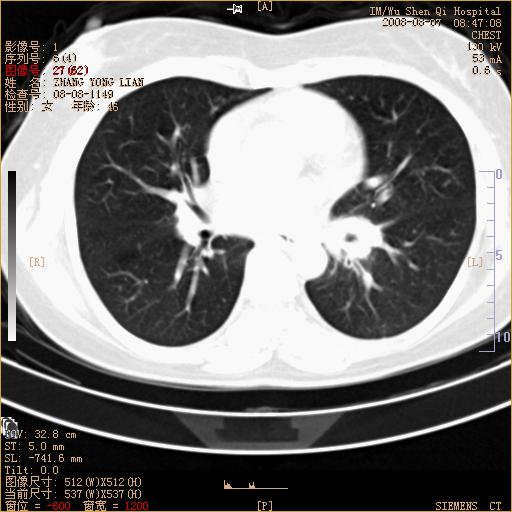

标题: CT15050:女,46岁,咳嗽胸痛一月余 [打印本页]

标题: CT15050:女,46岁,咳嗽胸痛一月余

纵隔窗没发全,左下肺近胸膜处结节。有长毛刺,纵隔淋巴结增大,不排除恶性病变。

考虑肺癌

考虑左肺下叶后基底段周围型肺癌伴纵隔淋巴结转移可能性大。

左下肺ca并纵隔及左肺门区淋巴结转移。

1)考虑左肺下叶后基底段周围型肺癌伴纵隔淋巴结转移。2)脾内低密度灶,性质待定;不排除转移瘤可能。

考虑左肺下叶后基底段周围型肺癌伴纵隔及肺门淋巴转移。